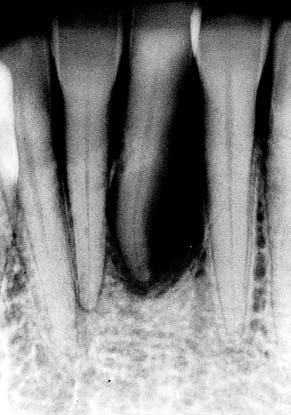

(図6)初診から33年経過(2008年1月7日)、71歳。咬耗は進んでいるが、骨植は堅固である

(図5)32年経過(2007年3月5日)、70歳。SPTの重要性とDiathermyの効果